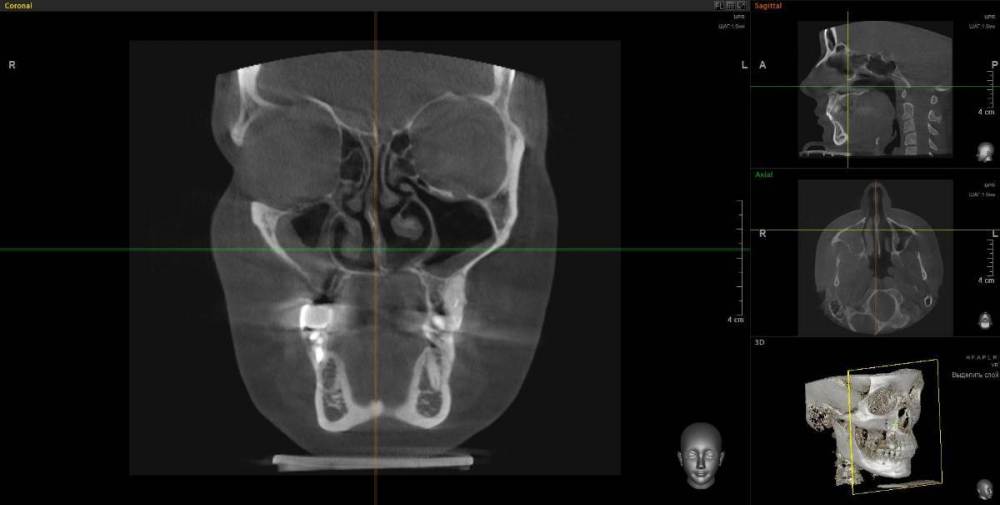

1. Сильное воспаление верхнего зуба привело к воспалению пазухи носа 2. Импланты 2 года (общая ст-ть 200 тыс.), тоже воспаление, рекомендовано удалить

1. Из-за сильного воспаления верхнего зуба костная кость растворилась и дошло до пазух носа. Зуб рекомендуют удалить

2. Импланты установила 2 года назад, в итоге заплачено было 200 тыс. с учетом циркониевых коронок. На КТ обнаружилось сильное воспаление, как следствие растворилась костная ткань импланты, доктор сказал уже не спасти.

Буду очень признательна за консультацию - действительно ли нужно удалять зуб и импланты? КТ во вложении

IMHO. Зуб 18 стоит удалить, зуб 17 стоит полечить. Имплантат в позиции 16, похоже, придётся удалить, имплантат в позиции 14, на мой взгляд, вне опасности.